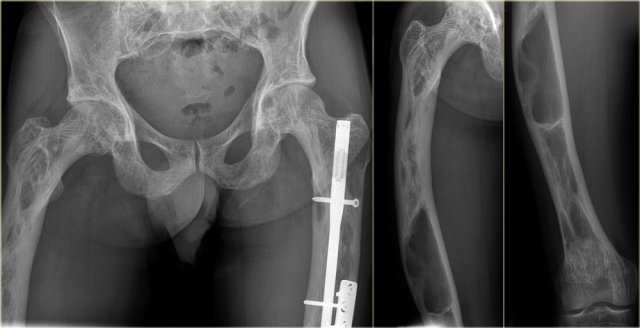

Fibrous dysplasia (2)

Here a polyostotic manifestation of FD.

There are multiple lesions, which are partially lytic and partially mixed lytic/sclerotic.

The radiographic appearance is determined by the extent of dysplastic bone and the amount of bone produced and the degree of calcifications and ossifications.

Fibrous dysplasia (3)

Fibrous dysplasia can be monostotic or polyostotic.

In this patient there are identical lesions within the proximal femur and left acetabulum.

There is a groundglass appearance with focal areas of calcifications.

Fibrous dysplasia (4)

The appearance of FD may vary from entirely lytic (probably due to cystic degeneration) to entirely sclerotic.

On the left images of a patient with polyostotic fibrous dysplasia, with lucent lesions in the proximal and mid-diaphyseal femur, and lesion with groundglass density and calcifications in the fibula.